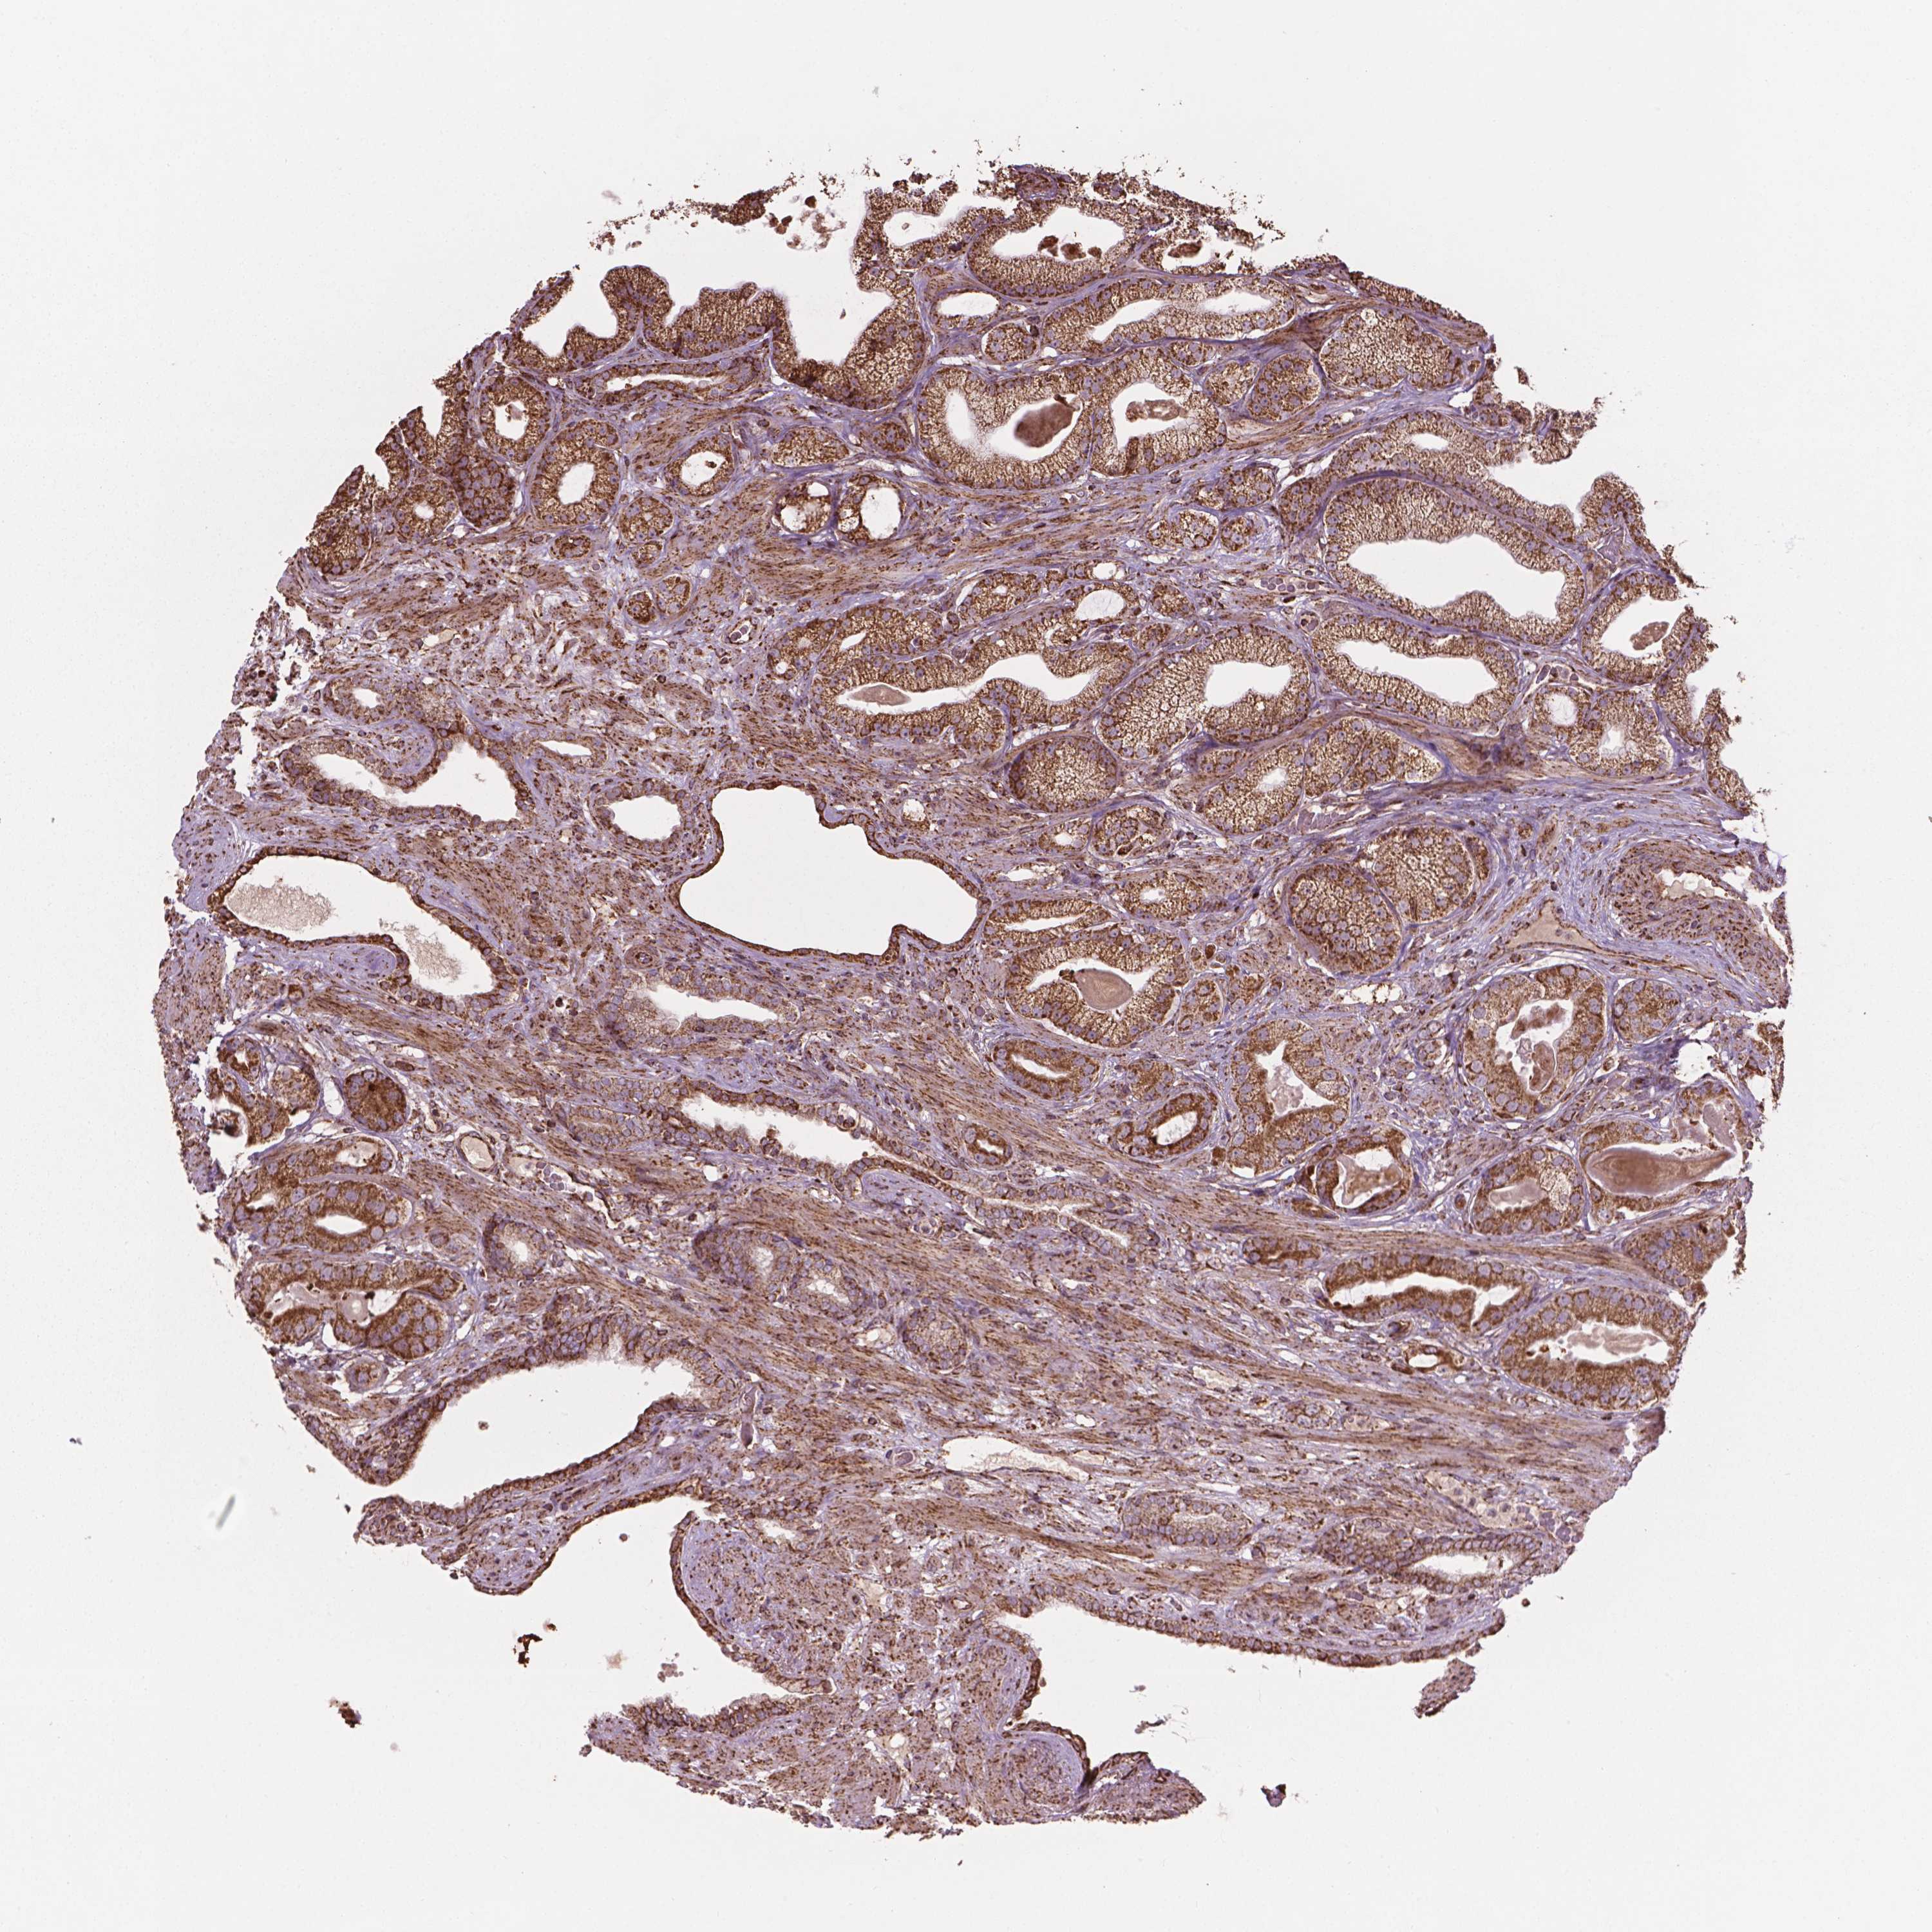

PROSTATE CANCER - Protein expressioni

A mouse-over function shows sample information and annotation data. Click on an image to view it in a full screen mode. Samples can be filtered based on level of antibody staining by selecting one or several of the following categories: high, medium, low and not detected. The assay and annotation is described here.

Antibody stainingi

Antibody staining in the annotated cell types in the current human tissue is reported as not detected, low, medium, or high, based on conventional immunohistochemistry profiling in selected tissues. This score is based on the combination of the staining intensity and fraction of stained cells.

Each image is clickable and will lead to virtual microscopy that enables deeper exploration of all samples and also displays staining intensity scores, fraction scores and subcellular localization as well as patient and tissue information for each sample.

Antibody HPA071530

Staining

High

Medium

Low

Not detected

Intensity

Strong

Moderate

Weak

Negative

Quantity

>75%

75%-25%

<25%

None

Location

Nuclear

Cytoplasmic/membranous

Cytoplasmic/membranous,nuclear

Adenocarcinoma, High grade

Adenocarcinoma, NOS

Adenocarcinoma, Low grade